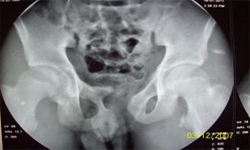

X Ray Showing Deformed Pelvis Scars of Multiple Pelvic Reconstructions